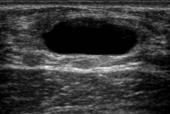

Fibroadenoma

Es la patología benigna más frecuente de mama y representa el 75%. Es una tumoración mixta de tejido estromal y epitelial del lobulillo mamario. Su manifestación es una masa bien definida de bordes regulares, blanda, no dolorosa, sin adenopatías axilares ni signos de flogosis. Es típico en las mujeres jóvenes y su tamaño suele ser menor de 3 cm. Se ubica sobre todo en el cuadrante superior externo. Se diagnostica con ecografía mamaria (ENARM 2007). Su manejo definitivo es la tumorectomía que se reserva para casos de mujeres mayores de 30 años, tamaños superiores a 3 cm, y que se presente sintomatología o que tengan algún factor que haga sospechar malignidad. En el resto requiere solo observación (ENARM 2017 A). (Ver Figura 20)